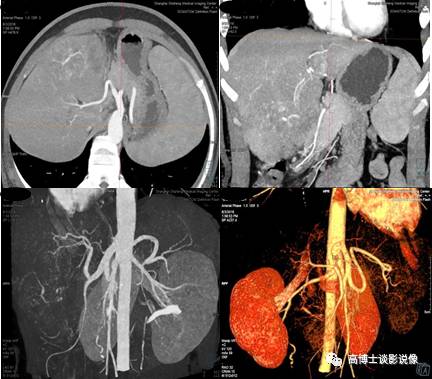

六、肾肿瘤血管术前评估

MIP重建显示肾脏肿瘤的供血类型、供血动脉、肿瘤血管团及有无动静脉瘘形成,显示动脉血管有无侵犯,显示肾静脉、下腔静脉内有无癌栓形成。去骨VR整体、直观显示双肾动脉整体解剖和变异血管起源、数目、走行等,判断其变异类型,显示有无异常血管团及狭窄、中断。为外科手术方案的制订、预防术中并发症及预测肿瘤的可切除率方面提供依据。